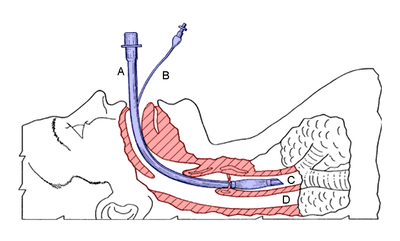

Diagram showing the result of a successful RSI: an endotracheal tube (blue) inserted into the trachea (C), protecting the lungs from regurgitation through the esophagus (D). | |

During this stage, laryngoscopy is performed to visualize the glottis. The endotracheal tube is then passed in between the vocal cords, and a cuff is inflated around the tube to hold it in place and prevent aspiration of stomach contents.

The position of the tube in the trachea can be confirmed in a number of ways, including observing increasing end tidal carbon dioxide, auscultation of both lungs and stomach, chest movement, and misting of the tube.